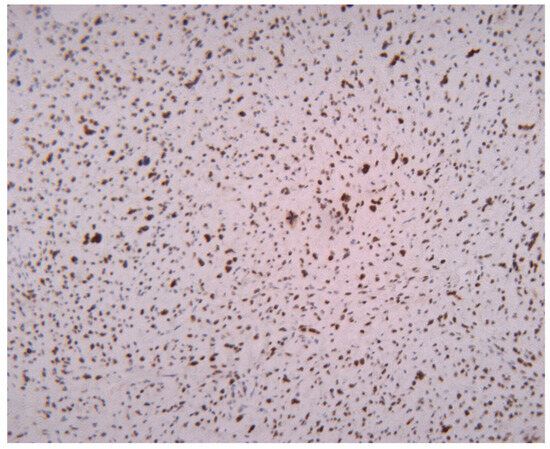

3.2. Proliferative Activity

3.5. Distribution of Liposarcoma Tumor Grades by Ki67 Proliferation Index